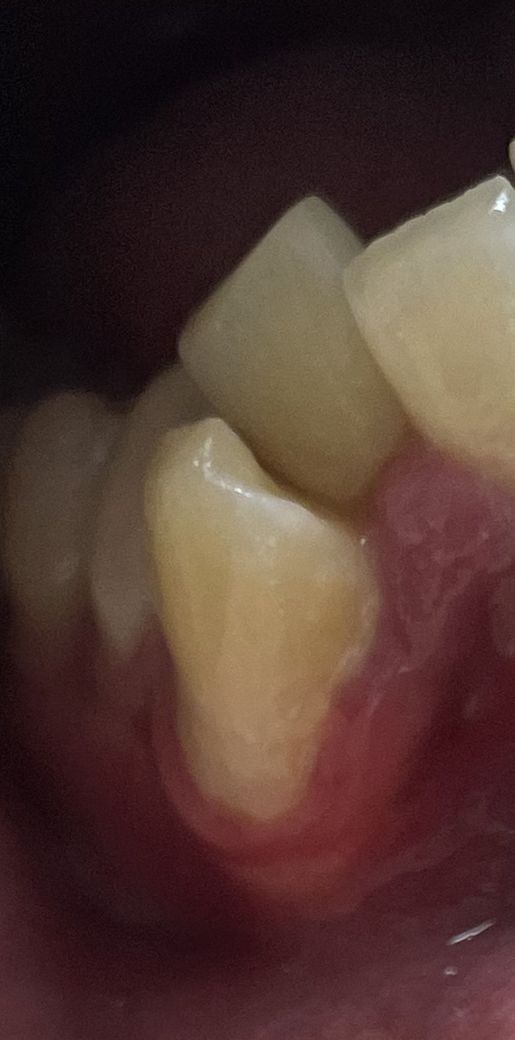

이빨이 고르지못해서 송곳니 위치가 빠질것같아 보이는데 그냥 둬도 문제는 없나요 ?

원래 이가 고르지못해서 삐뚤했는데 오늘 보니까 예전에 비해 잇몸이 송곳니를 다 감싸지못하고있는것같은 느낌이 들어서요 이대로 그냥 둬도 큰 문제는 없은건가요 ?? 사진 첨부해드리겠습니다 !

송곳니가 덧니로 되어 있습니다. 덧니라도 빠지고 하는 일은 없습니다.

덧니가 되어 있어면 틈에 음식물 찌꺼기가 잘 끼고, 치솔질 잘 안되니 충치가 생기기 쉽습니다.

현재 사진만으로는 정확한 판단이 어렵습니다. 치아는 전반적인 치열 배열과 함께 평가해야 합니다. 다만 현재로서는 부정교합으로 보여지며 교정 등을 해야할 것으로 보여집니다. 그대로 방치 시 치열이 더 많이 틀어지거나 이상이 생길 가능성이 있으므로 가까운 시일 내에 치과 방문을 해보시길 바랍니다.

송곳니는 뿌리가 매우 길기 때문에 사진처럼 보여도 턱뼈안에 잘 고정되어 있는 경우가 많습니다.

하지만 치아 사이에 이물질이 많이 껴서 충치나 치주질환이 생길수 있는 형태이기 때문에 칫솔질과 치실을 같이 하는것이 좋습니다 .

송곳니가 덧니인것으로 보입니다.

현재 바깥쪽으로 이소맹출했기 때문에, 이 경우 바깥쪽 잇몸뼈가 얇아서 잇몸이 올라가는경우가 많이 있습니다. 하지만 현재 문제될정도는 아닌것으로 보입니다.

우선 양치질을 잘 해주시는게 좋으며, 잇몸가까운부위가 마모되는 경우도 있고, 이 경우 그 부위를 때울 수 있습니다.